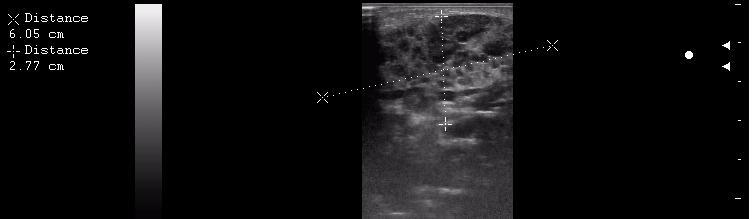

интранодулярные лимфоузлы в околоушной железе

иногда я меряю так, и немножко ошибаюсь)

размер железы 30,8 + 34 = 64,8 мм х 20,4 мм